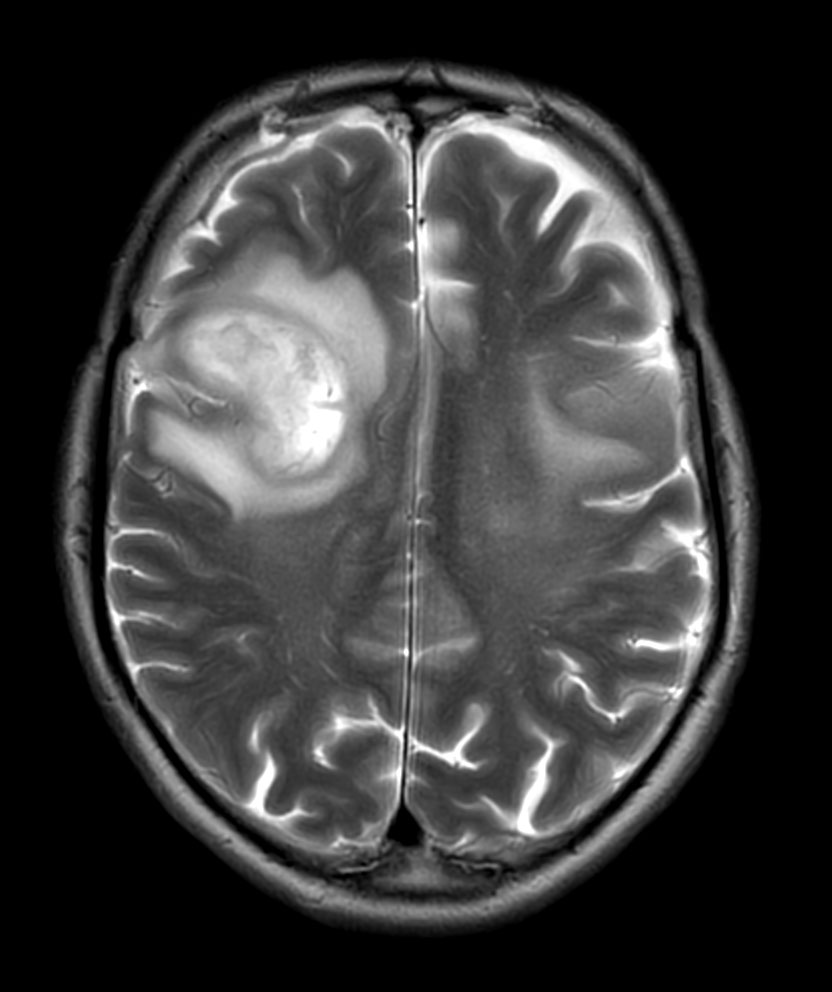

Patient with a revasculerized area with small bleedings. Diagnosed as malignant glioblastoom.

Axial T2w MultiVane XD